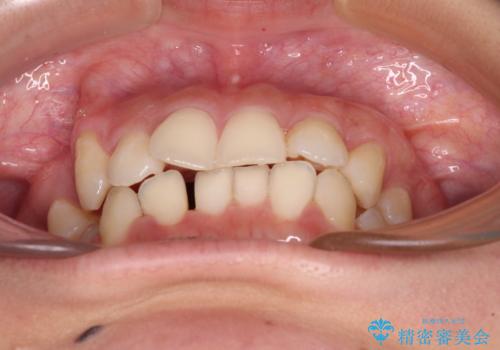

- 八重歯と上顎正中のズレを気にして来院された患者様です。

インビザラインによる矯正治療を希望されたため、八重歯改善のための抜歯矯正部分や上顎正中の大幅に位置移動は、補助装置やワイヤー矯正を併用し、その後はインビザラインにて行うこととしました。

骨格的に下顎が左側に変位していたため、上下正中を合わせることは困難であることは分かっていましたが、可能な限り合わせることができました。